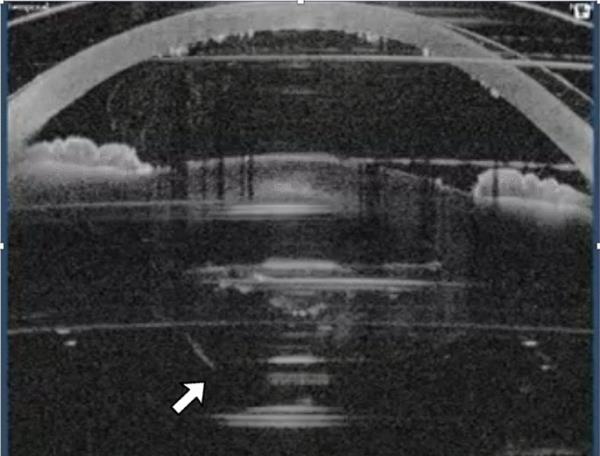

图1

figure 1

囊膜切开后眼倾斜,此时碎片量已经设定。这导致后囊部分被飞秒激光切割